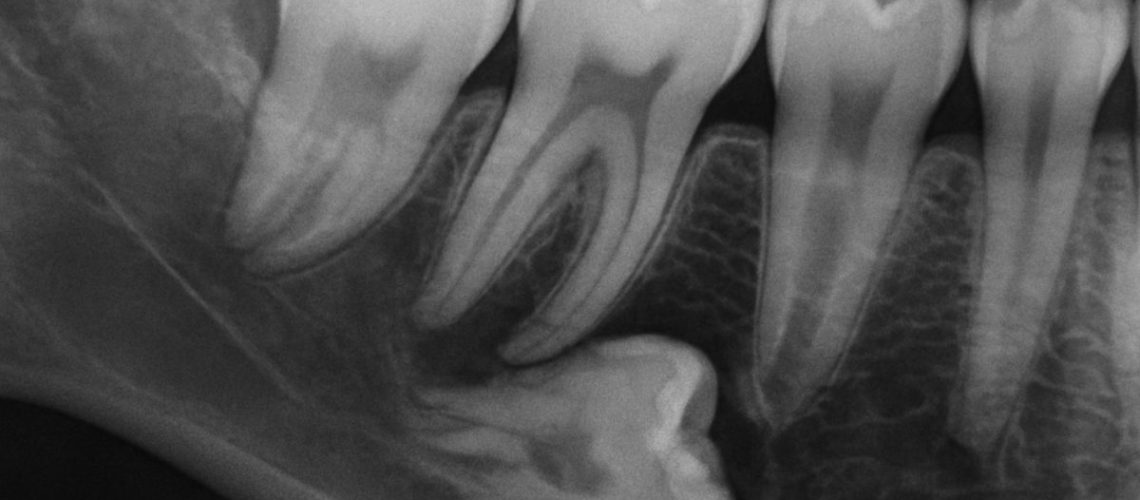

A close-up x-ray of bottom wisdom teeth impacted in the jaw, with one tooth pressing against the adjacent molar, causing potential damage. No text on image.

Lower back wisdom teeth can be fully impacted (still covered by bone), partially erupted (partly through the gum), or angled (tilting forward, backward, or sideways). Angled or impacted lower back wisdom teeth can press on the tooth in front, trap food and bacteria, or create pockets where infections start. The deeper the impaction and the closer the roots to the nerve, the more complex the extraction may be.

Evaluation starts with a clinical exam of the mouth and gums. Imaging is essential: a panoramic X-ray shows overall tooth position and root length, while CBCT (3D cone beam) imaging shows exact root shape, nearby bone, and the relationship to the inferior alveolar nerve. 3D imaging can change the treatment plan—for example, revealing that a tooth thought to be simple will be close to the nerve and needs a specialist or different anesthesia.